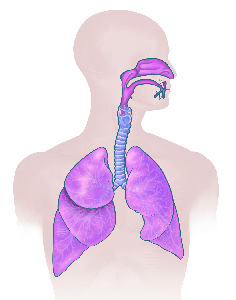

Detailreiche Fotografien aus der medizinischen Praxis ergänzen die Texte; moderne, genaue,

wissenschaftliche Zeichnungen geben Einblick in die Anatomie und die Funktion der Lunge und

anderer Organe.